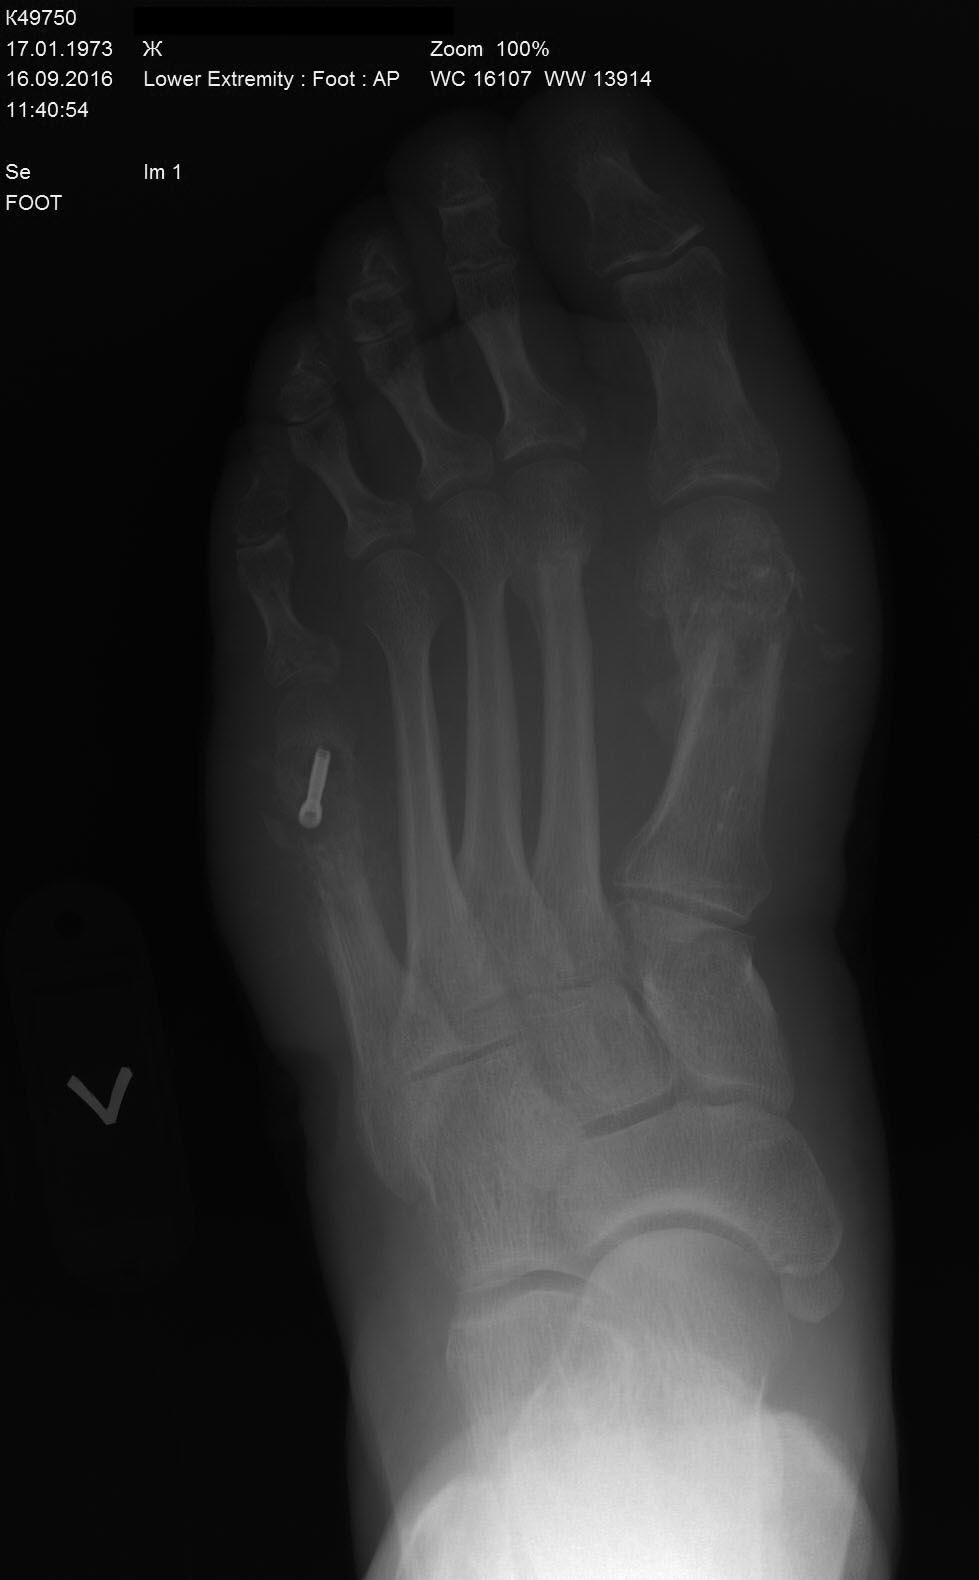

Пациентка 40 лет. Оперирована в июне 2016г- реконструктивная операция на 1-й плюсневой кости левой стопы по поводу вальгусной деформации 1-го пальца и на 5-й плюсневой по поводу деформации Тейлора. В стационаре после операции провела 5 дней, выписана в удовлетворительном состоянии со спокойными п/о ранами. Через 6 недель у пациентки в области п/о рубца в проекции 1-й плюсневой кости открывается свищ. Пациентка амбулаторно перевязывается.

Через 8 недель на Р-контроле выявляется миграция винта в 1-й плюсневой кости, который амбулаторно удален. Пациентка в этот момент жалуется только на отечность переднего отдела стопы и отделяемого свища. Лихорадку пациентка отрицает. В крови С-реактивный белок в норме, лейкоцитарная формула тоже в пределах нормы.

Через 10 недель пациентка приносит Р-контроль где имеются отчетливые признаки резорбции костной ткани в 1-й и 5-й плюсневых костях.